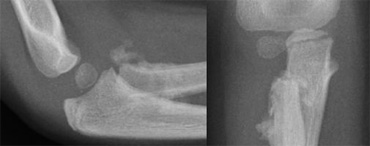

Flexion-type supracondylar fracture caused by direkt impact Flexion-type supracondylar fracture caused by direkt impact

Supracondylar fractures (5)

Flexion-type fractures are uncommon (5% of all supracondylar fractures).

They are caused by direct impact on the flexed elbow.

Ulnar nerve injury is more common.

Compared to extension types, they are more likely to be unstable, so more likely to require fixation.